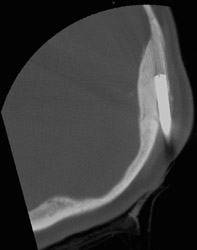

A bone biopsy of skull lesions can be done percutaneously with CT guidance. Such a biopsy might be needed in patients who have a history of cancer and who develop new lesions seen on bone scan and/or CT scans. Via a mini incision, a bone trocar is used to obtain a bone biopsy of the suspected abnormal skull bone.